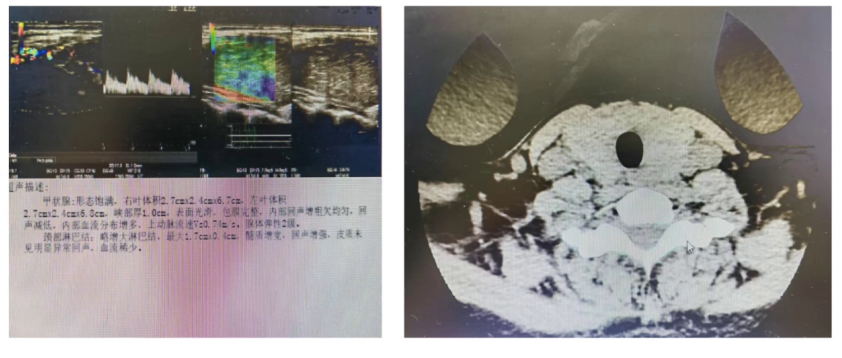

(3)影像学检查

甲状腺彩超显示甲状腺弥漫性病变,符合Graves病甲亢高代谢状态表现,甲状腺血流速度0.74m/s,明显高于正常范围。

肝胆胰脾及泌尿系超声未见异常,胸部CT提示双肺小结节影,甲状腺CT未见占位性病变。